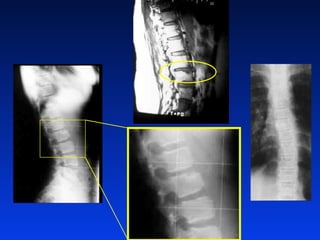

HÌNH AÛNH HOÏC COÄT

SOÁNG

• X quang vuøng baûn leà

• X quang nghieâng

• X quang chöùc naêng

• Ñaùnh giaù tình traïng taêng tröôûng (Risser,

tuoåi xöông)

• Nhaáp nhaùy ñoà xöông: neáu (+) coù gaõy

meät; coù theå chöõa laønh vôùi neïp thaân

HÌNH AÛNH HOÏCCOÄT SOÁNG • X quang vuøng baûn leà • X quang nghieâng • X quang chöùc naêng • Ñaùnh giaù tình traïng taêng tröôûng (Risser, tuoåi xöông) • Nhaáp nhaùy ñoà xöông: neáu (+) coù gaõy meät; coù theå chöõa laønh vôùi neïp thaân